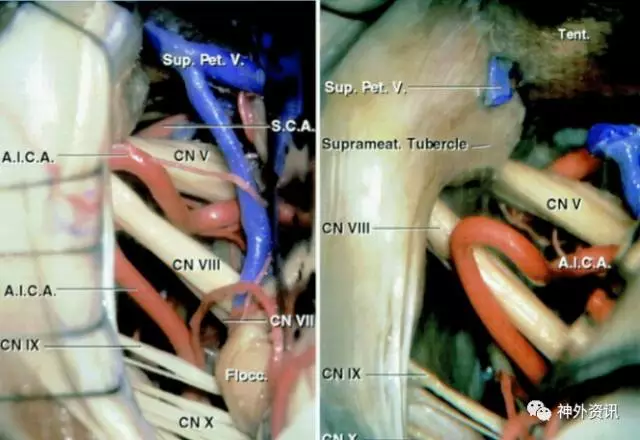

下列图片阐述了相关手术解剖。

图4.乙状窦后入路暴露左侧桥小脑角区脑血管结构。需要注意的是,三叉神经在术野深处,离术者更远。面听神经复合体位置相对表浅,自下斜向上走行。这些解剖知识帮助术者更容易辨别这些神经。

图5. 三叉神经和小脑上动脉(SCA)的关系。三叉神经后根在SCA下方进入脑桥中部(A)。SCA向下成袢,与三叉神经后根在其入桥脑处接触(B)。袢主干的头端分叉后向下在三叉神经的上表面形成压痕(C)。SCA向上分叉并离开三叉神经(D)。